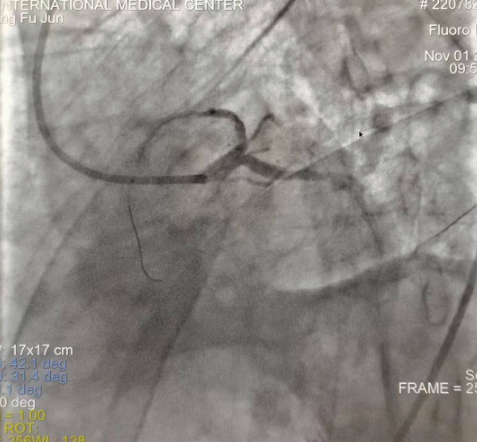

閉塞的血管再通時(shí)間取決于急救時(shí)長(zhǎng)、轉(zhuǎn)運(yùn)時(shí)長(zhǎng)和治療時(shí)長(zhǎng),在前兩方面,醫(yī)院已為患者爭(zhēng)取了最短時(shí)間。患者家屬遠(yuǎn)在陜北,雖然已在趕來(lái)的路上,但最快抵達(dá)西安也要3小時(shí),在與患者家屬電話溝通同意急診手術(shù)后,醫(yī)療總值班代家屬簽字,康曉軍在請(qǐng)示心臟病醫(yī)院王海昌院長(zhǎng)及心臟內(nèi)科CCU尚福軍主任后,積極進(jìn)行術(shù)前準(zhǔn)備。在沒(méi)有家屬陪同、沒(méi)有交費(fèi)、沒(méi)有辦入院手續(xù)的情況下,患者經(jīng)胸痛中心綠色通道被送往心臟冠脈介入手術(shù)室,打通了完全閉塞的心臟前降支近段血管。